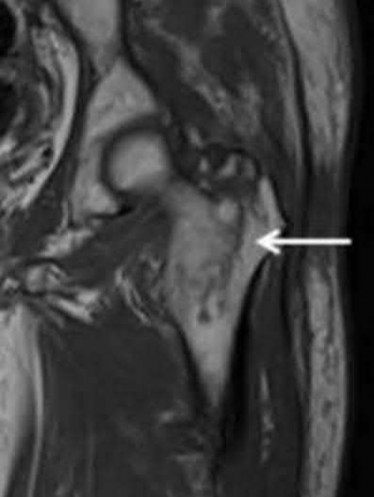

Question 13:

A 65-year-old male presents with neurogenic claudication. He reports pain radiating down both legs when walking, which is relieved by leaning forward on a shopping cart. MRI shows severe spinal stenosis at L4-L5. Which ligament thickens and contributes significantly to the dorsal compression of the thecal sac in this condition?

Correct Answer: Ligamentum flavum

Explanation:

In degenerative lumbar spinal stenosis, hypertrophy and buckling of the ligamentum flavum commonly cause dorsal compression of the thecal sac.